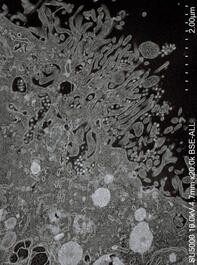

COVID-19 virus. microscope images. From the book Virus. 2020....

COVID-19 virus. microscope images. From the book Virus. 2020.

VIRUS. Book. 2020.